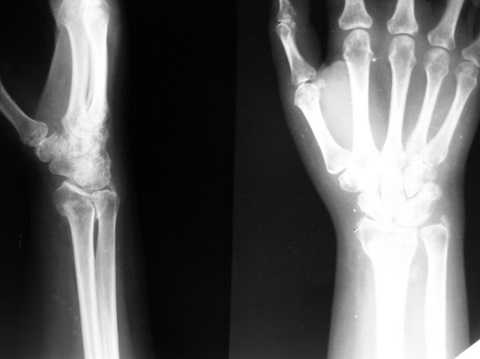

Лечилась: гипсовая иммобилизация 4 нед, препараты кальция. В реабилитационном периоде получала ЛФК, изотерапию, медикаментозные болкады. На данный момент женщину беспокоят слабокупирующиеся боли плечо-локоть-кисть по локтевой поверхности больше, ограничение движений в л\з суставе и мелких суставах кисти (см приложения: общий вид, объем движений,

на Ргр нарастают явления остеопороза, не смотря на прием препаратов кальция.

Видимо там был оскольчатый перелом луча и шиловидного отростка

локтевой кости.

В гипсовом повязке наблюдалось вторичное смещение костных отломков по длине (при передне-заднем рентгенограмме), и при боковй проекции видно смещение отломка в дорсальном направлении и таким

образом последный дает компрессию нервов в лучезапястном канале (типа синд. Зудека)

Это видно и клинически.

Этого синдрома купировать почти невозможно на долгий срок, потому что идет постоянная компрессия в канале. остеопопроз это из-за нарушения

иннерваций область кисти.